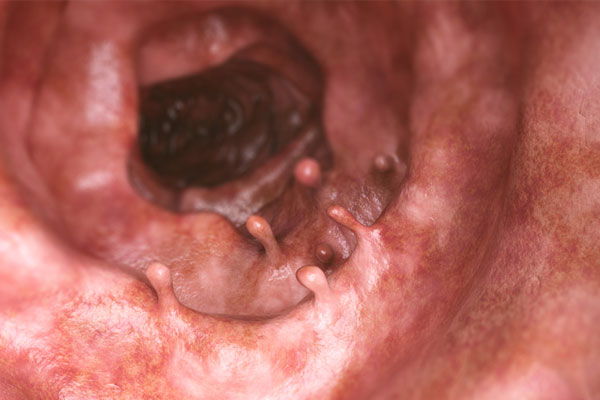

Médicos Especialistas - Gastroenterología